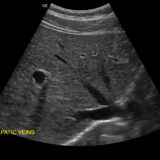

- 腹部エコー

腹部・心・下肢のポータブルエコー運用 - 内科・循環器内科クリニック

胆のう・膵臓・肝臓の走査標準化